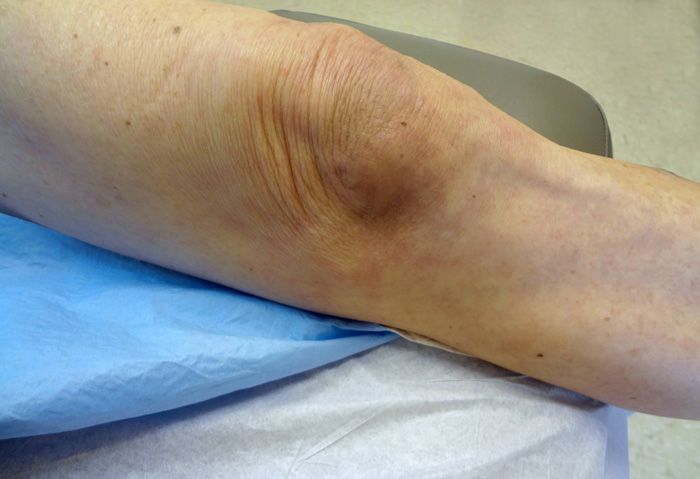

Question 3:

A 28-year-old man sought medical attention for a minimally pruritic “rash” on both knees. The eruption consisted of well-demarcated erythematous plaques covered by silvery scale.